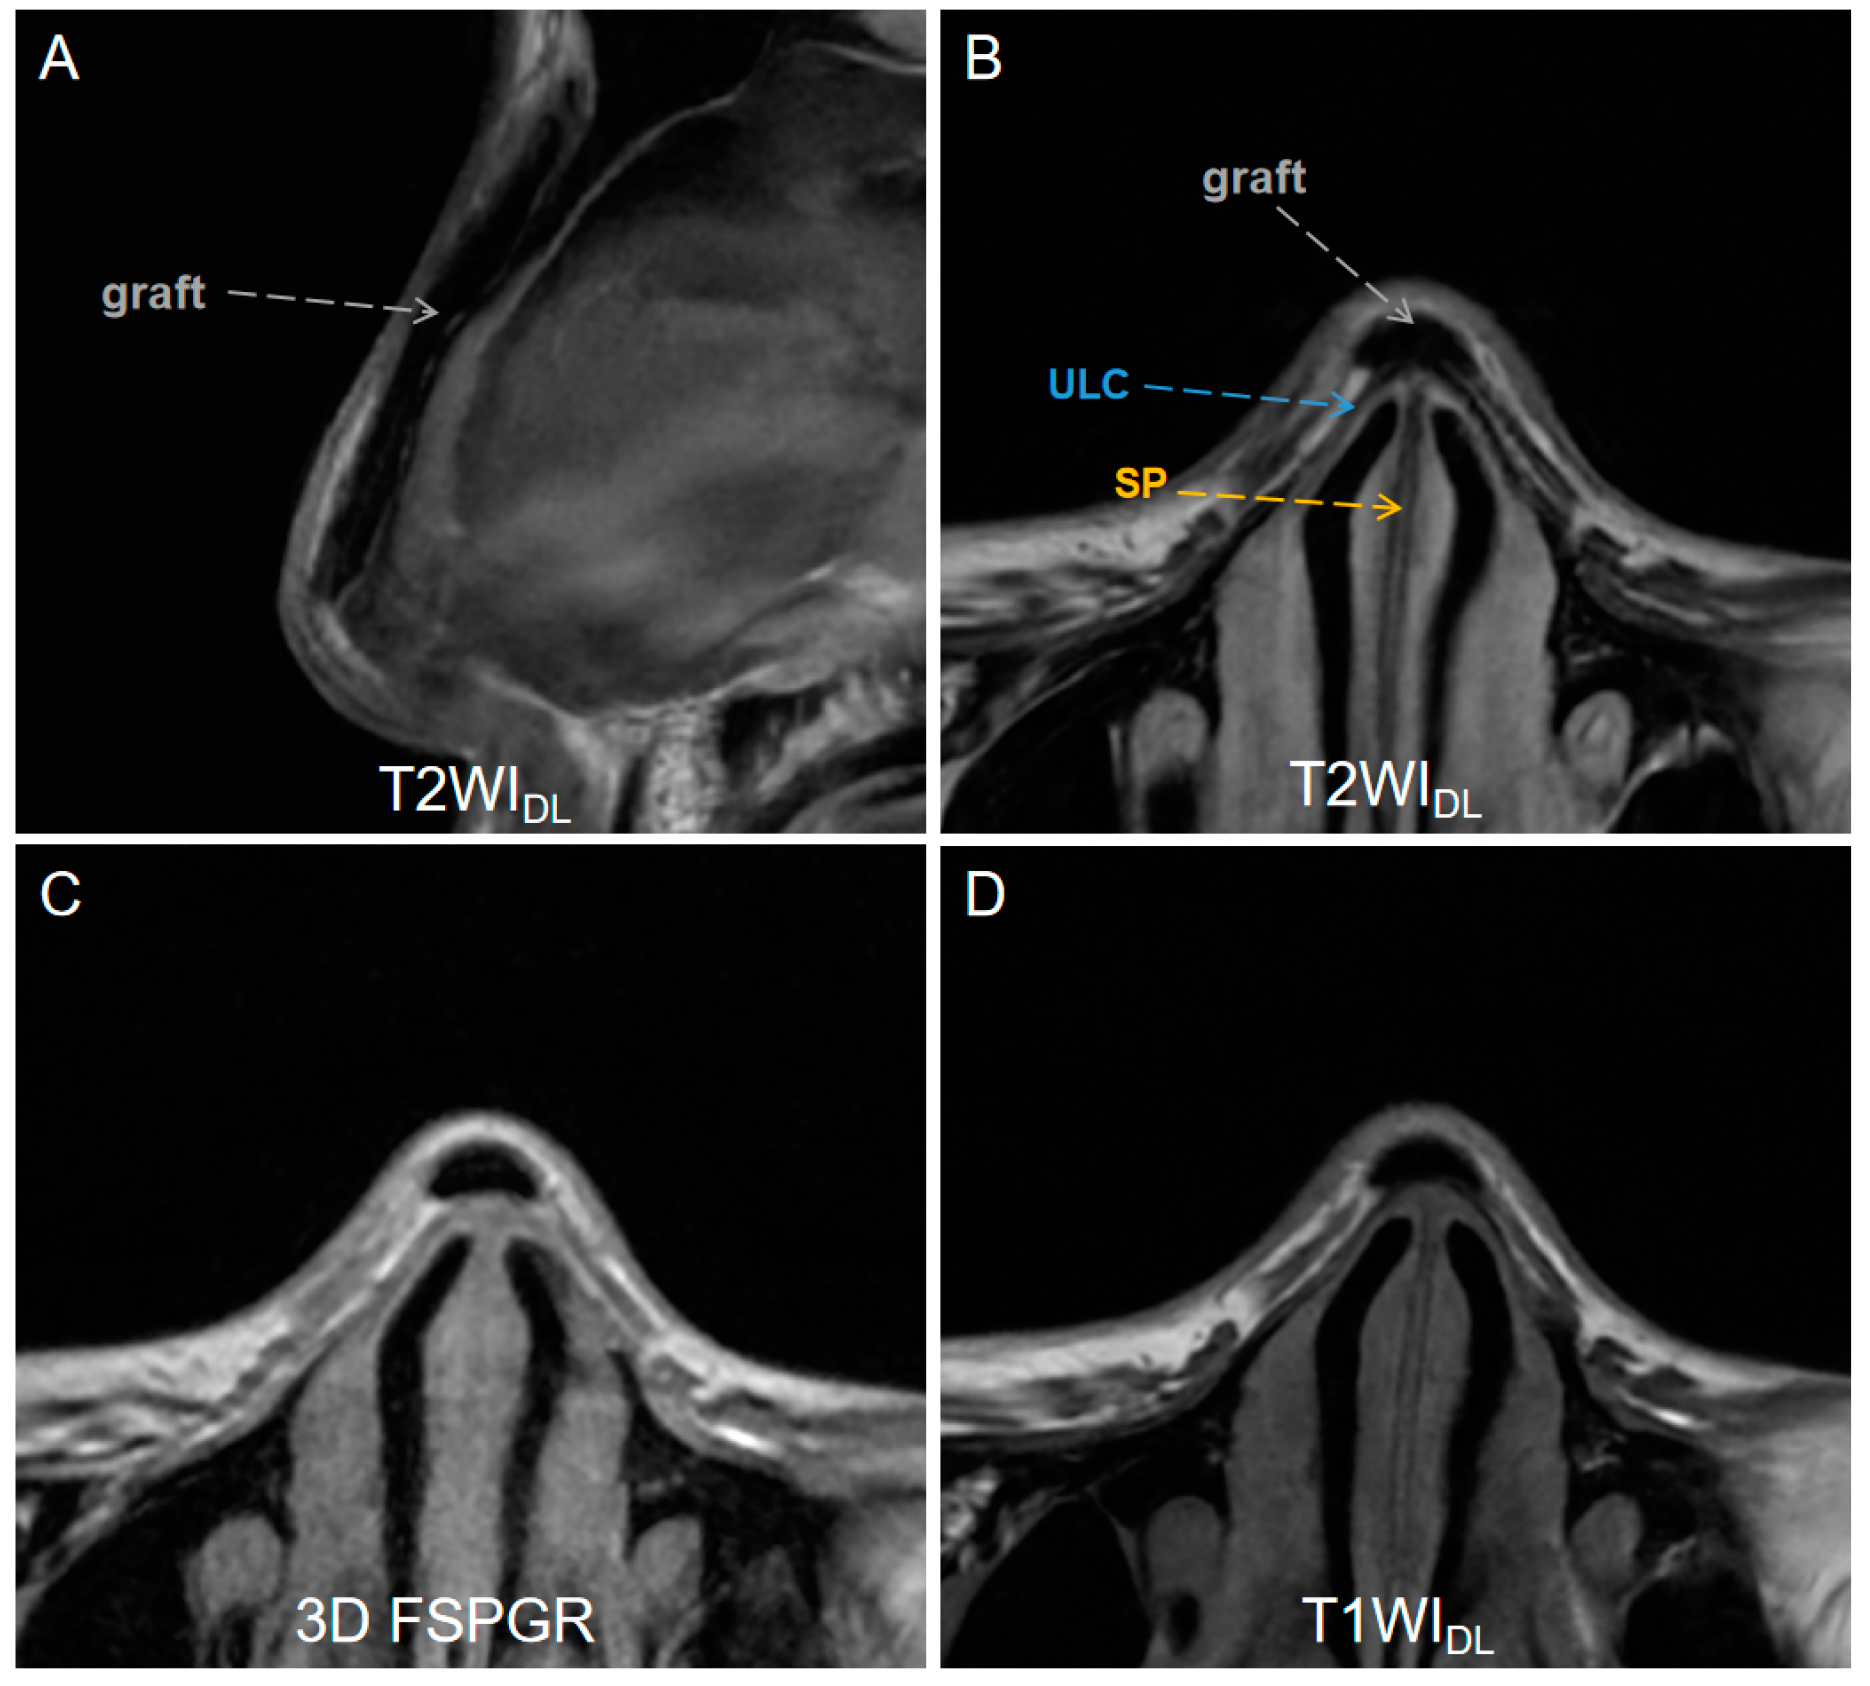

A total of 38 patients (10 men and 28 women, mean age = 25.5 ± 2.3) with complete MRI datasets were included after excluding 9 for nasal trauma or tumors and 4 for incomplete MRI data among 51 volunteers. Characteristics of the study patients and indications for maxillofacial MRI are shown in Table 2. Figure 2 illustrates the MR images of a patient who underwent augmentation rhinoplasty with autogenous ear cartilage graft after one year.

Figure 2.

A low-signal-intensity graft (gray dashed arrows) on (A) sagittal T2WIDL image (DLR T2-weighted FSE images), (B) axial T2WIDL image, (C) axial 3D FSPGR image (three-dimensional fast spoiled gradient-recalled images), (D) T2WIO (original T2-weighted FSE images), and (D) axial T1WIDL (deep learning–reconstructed T1-weighted FSE images) image of a 26-year-old female who underwent an MR examination one year after receiving augmentation rhinoplasty with autogenous ear cartilage. T2WIDL shows a clearer boundary between the graft and the tissue. DLR = deep-learning-based reconstruction, SP = septal cartilage (yellow dashed arrow), ULC = upper lateral cartilage (blue dashed arrow).